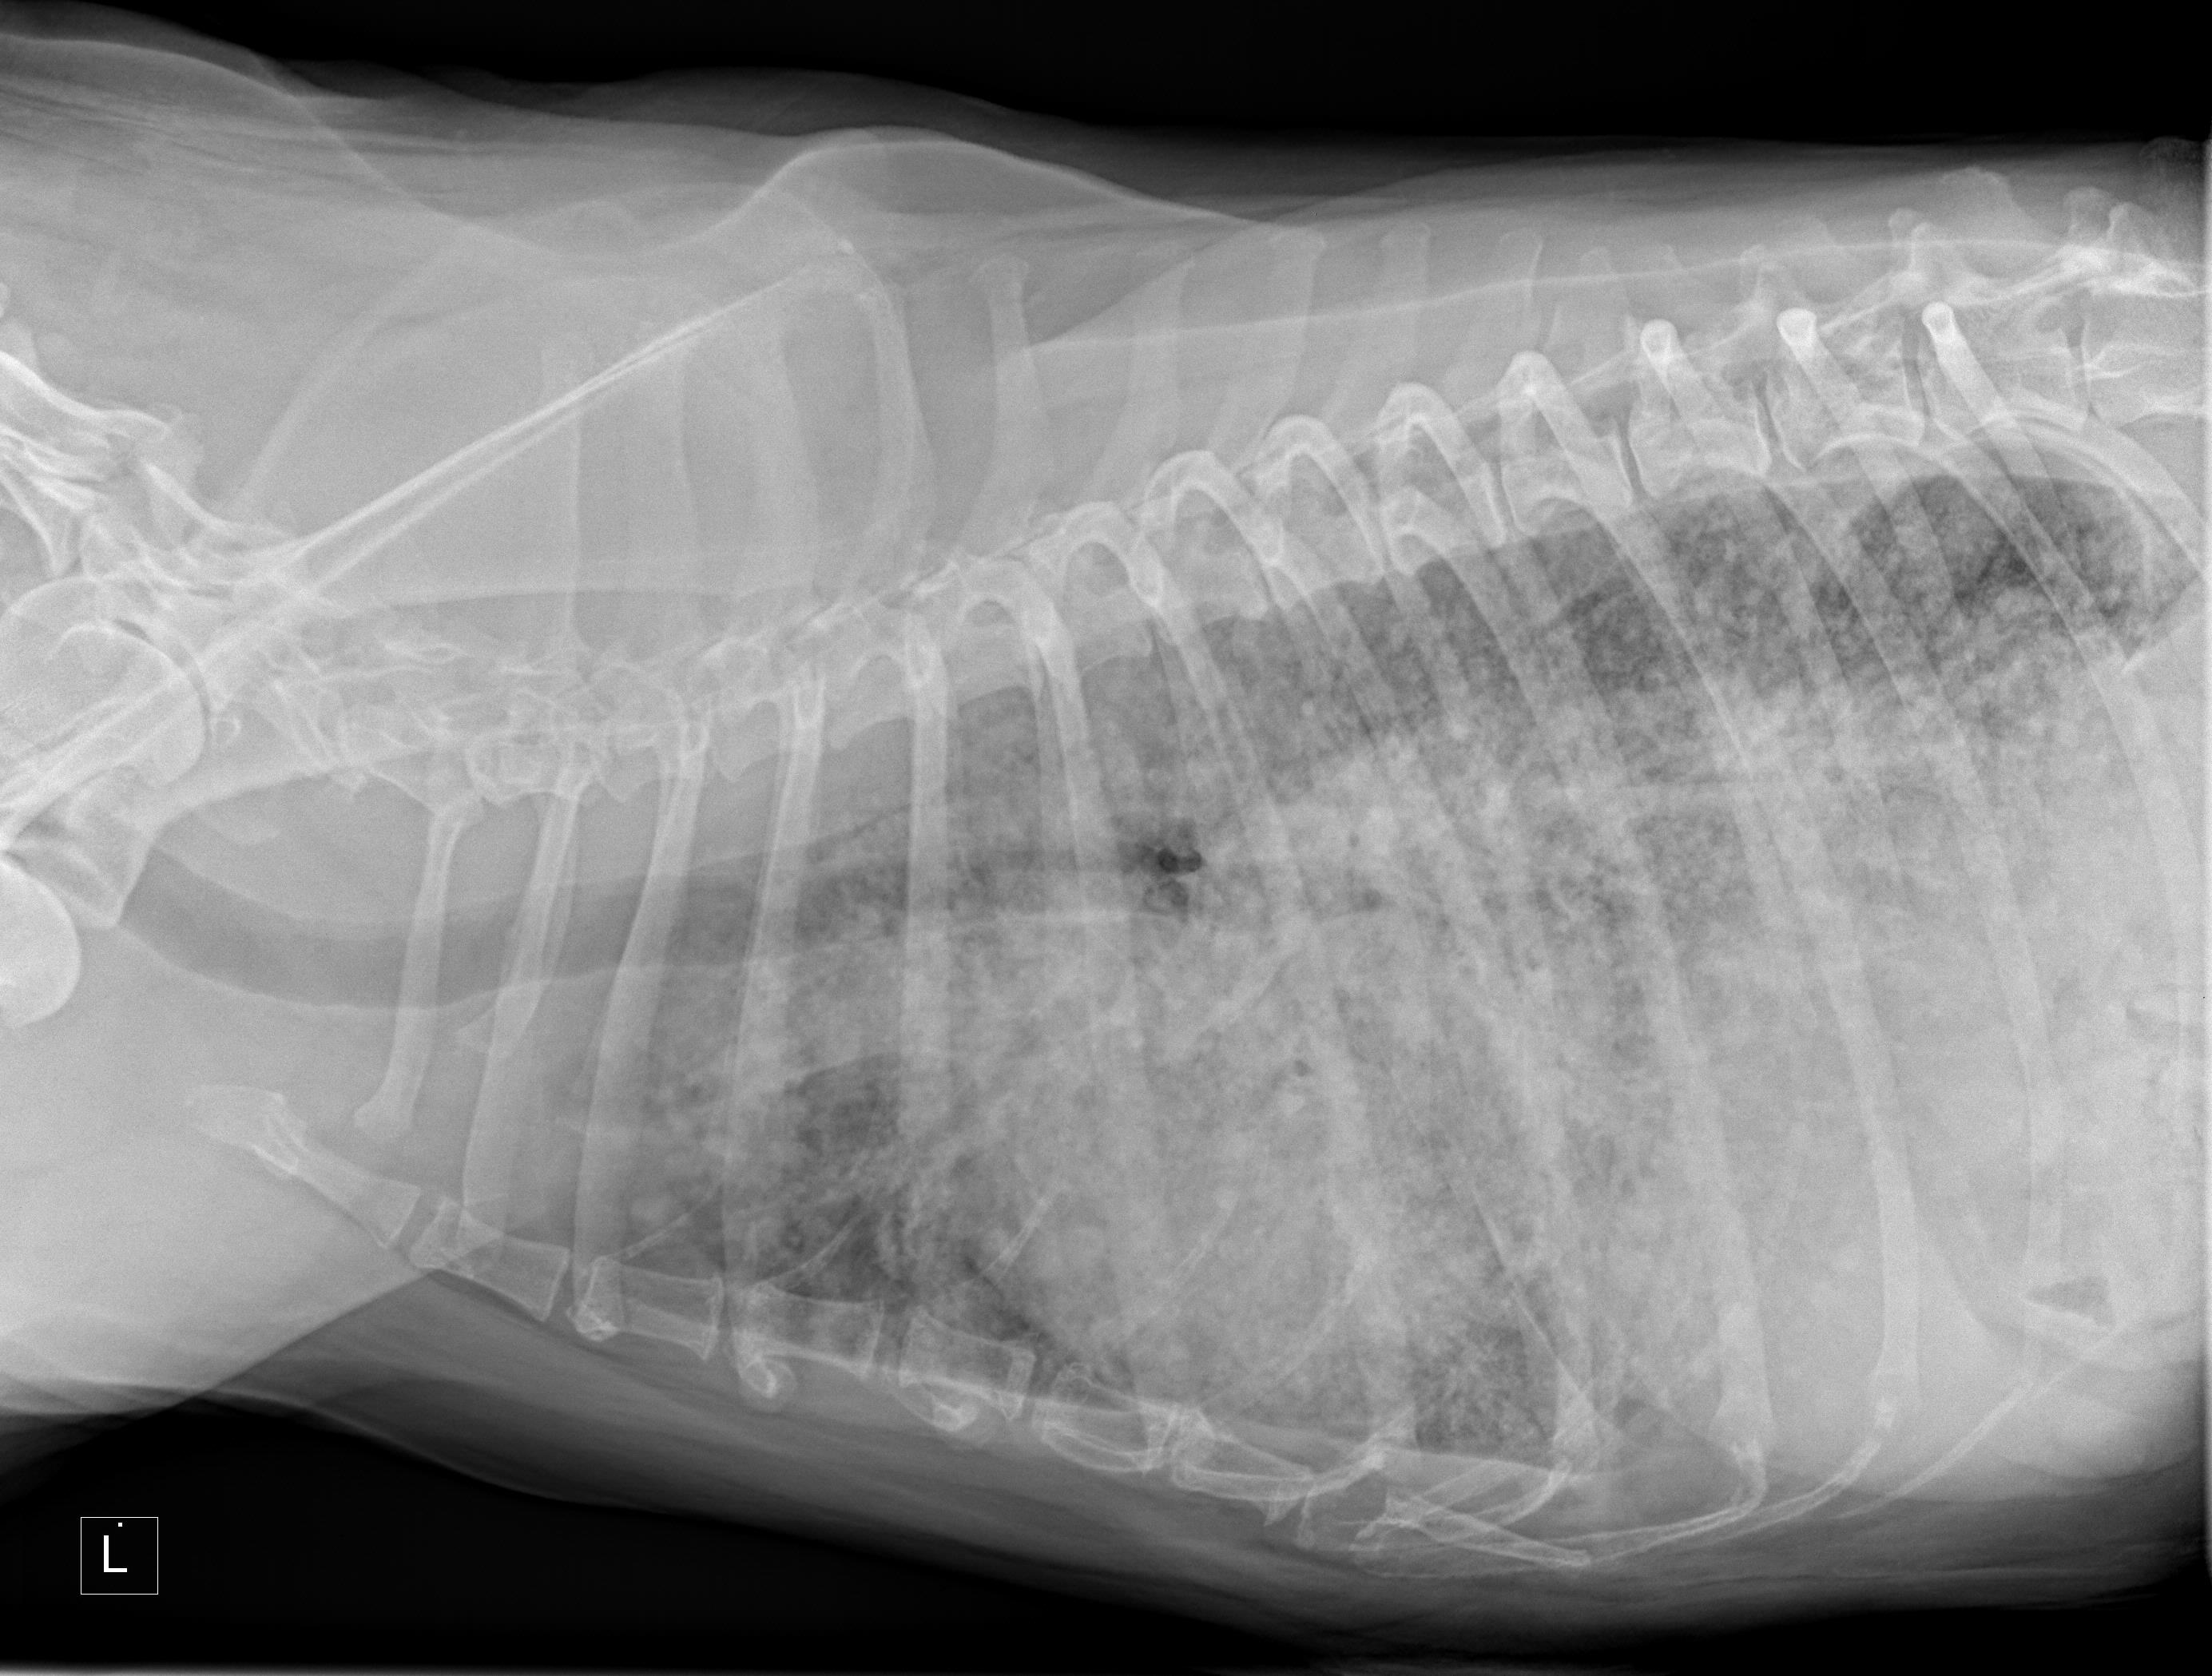

This can be more readily seen if I publish the xray image of yesterday and the image taken on the 15th April; see below.

Xray image as of the morning of May 12th, 2016.

Despite not truly understanding these images both Jean and I quickly thought the top one, taken yesterday, showed a decline in Hazel’s lungs compared to the lower one, taken on the 15th April.

Dr. Winters couldn’t be sure without a physical examination of the lung tissue but on the balance of probability she believed Hazel was at an advanced stage of cancer with the tumor somewhere in the body and that her lungs were showing that the cancer had metastasized!

One of the radiographs taken of Hazel.